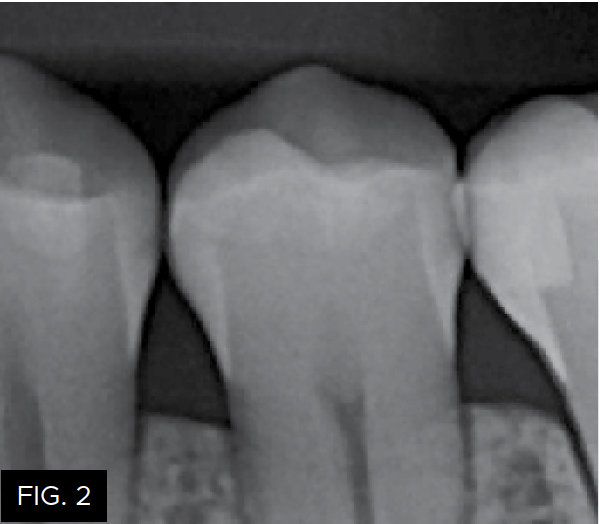

The patient shown in FIG. 1 presented with radiographic decay (FIG.2 and 3) on the distal surfaces of tooth numbers 19 (36) and 21 (34).